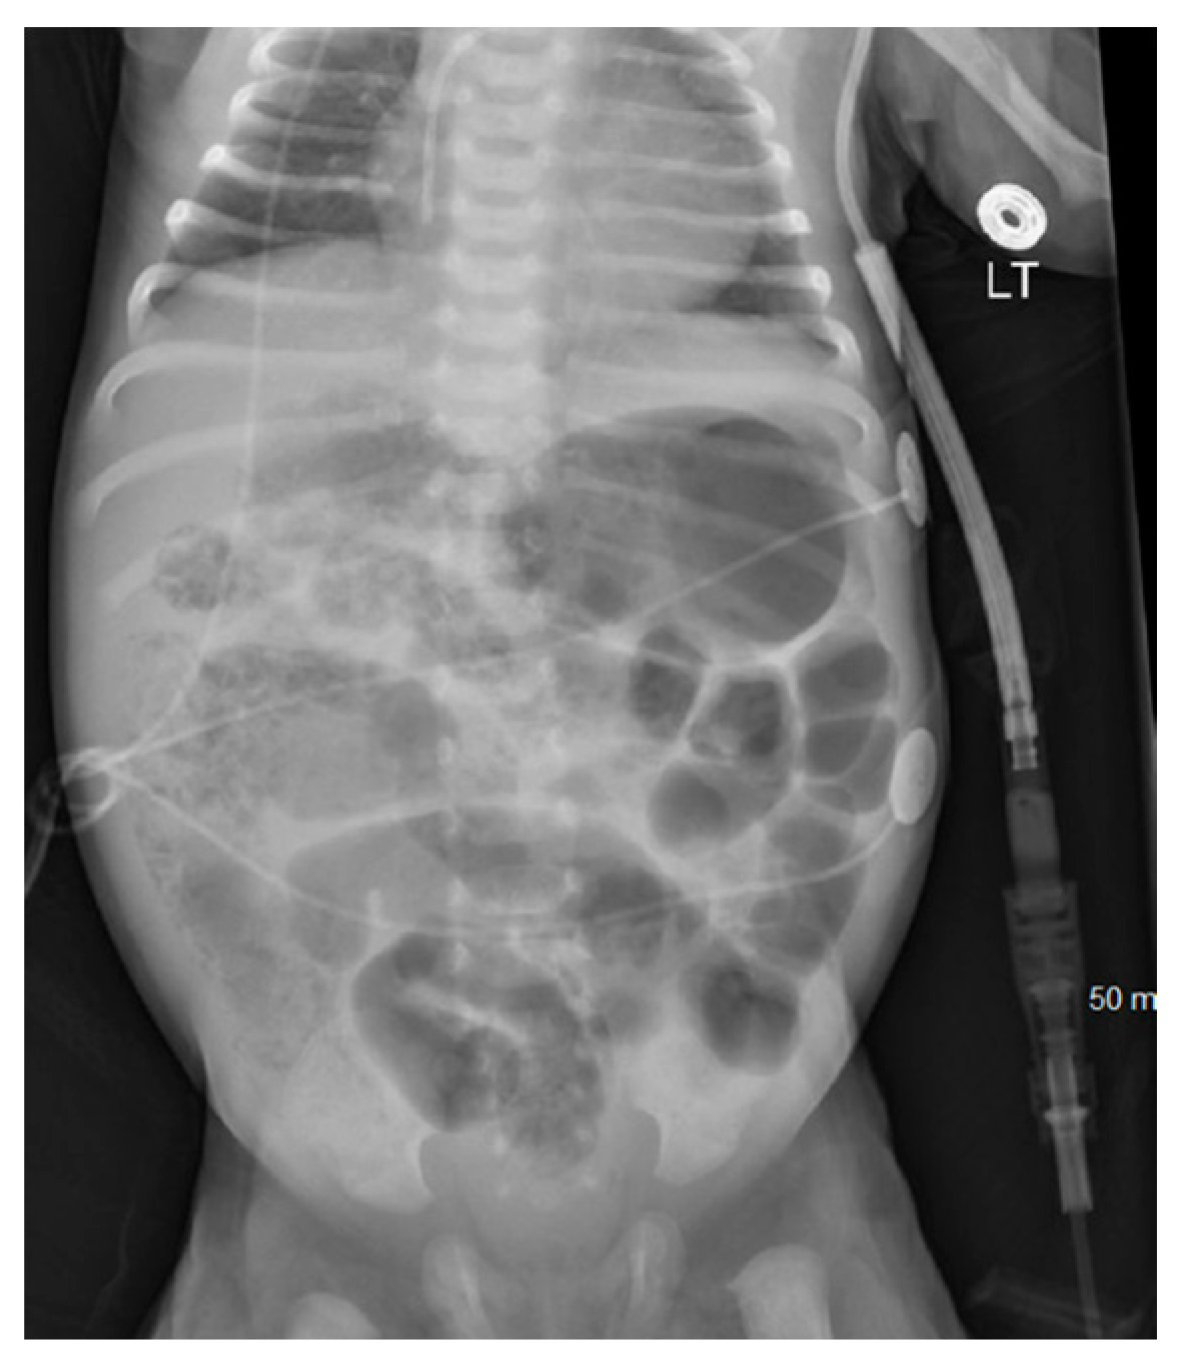

On DOL 41, the infant developed abdominal distension and tenderness, with AXR showing pneumatosis with portal venous gas (Figure 4a), suggesting recurrent NEC later progressing to featureless bowel loops (Figure 4b). The infant developed significant ascites with marked edema along with shock, necessitating a saline bolus, dopamine, multiple transfusions, and antibiotics (Vancomycin, Piperacillin-Tazobactam, and Metronidazole). An exploratory laparotomy on DOL 51 involved abdominal washout, drainage, and temporary closure of perforated intestinal loops. Due to extensive inflammatory phlegmon, double-barrel intestinal stomas were created, and the abdomen was left open for healing and covered with a sterile dressing under a transparent adhesive film, with the repaired loop positioned beneath. Wound cultures from ex-lap grew Klebsiella, leading to a change in antibiotics to Meropenem.

Figure 4. Abdominal X-ray on Day 41 and Day 50 suggesting recurrent necrotizing enterocolitis; (a) Day 41 abdominal X-ray revealing pneumatosis with portal venous gas; (b) Day 50 Abdominal X-ray revealing abdominal distension with featureless bowlet loops.